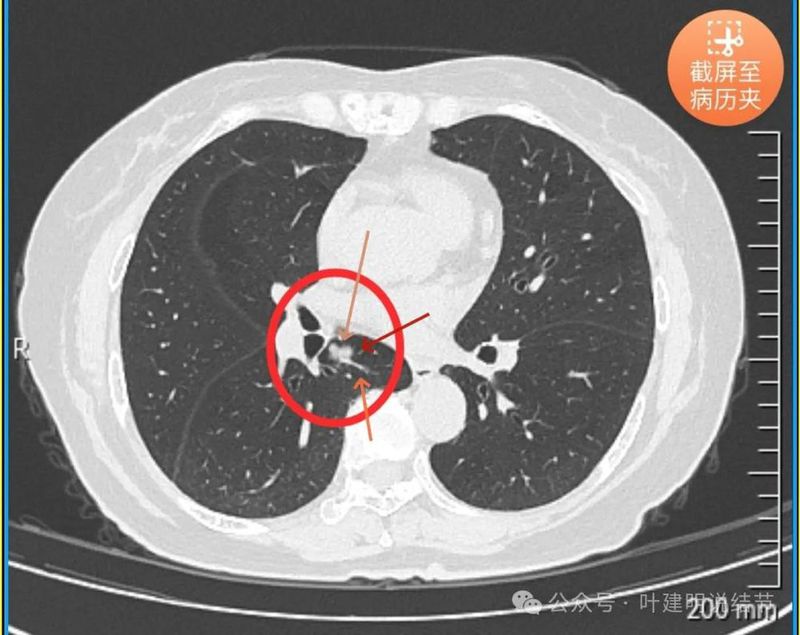

再看2024年5月时复查的影像:

分叶,混合偏实性密度,血管贴边走行。

与支气管紧贴,黄色箭头所示处似乎支气管壁与病灶已经愈着。

上图又见结节与支气管不是都愈着的,说明侵袭性并不强,病灶表面光滑。

天蓝色箭头所指处是北段支气管与病灶之间,感觉较2月份贴得近了一点点。病灶表面仍是光滑的,总体感觉有膨胀性。

病灶边缘光滑,有血管穿出来似的。

表面光滑,有膨胀性。

内部密度较为均匀,就位于肺门部。

边缘光滑,实性,有膨胀感。

与血管关系近。

边缘区域与下肺静脉间隙不太清楚。